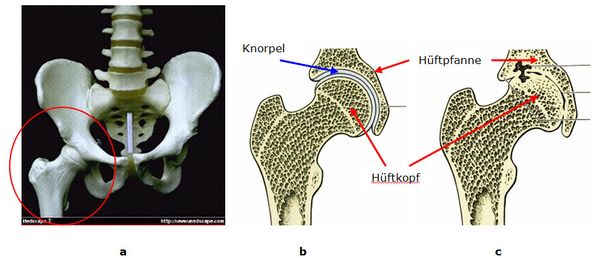

Abb. 2: a Becken mit rechtem Hüftgelenk (roter Kreis).

b Das Hüftgelenk ist ein Kugelgelenk und besteht aus den Komponenten Hüftpfanne und Hüftkopf. Die Hüftpfanne bildet eine kugelförmige Schale in der der Hüftkopf in allen Ebenen bewegt werden kann. Beide Knochenflächen sind mit Gelenkknorpel belegt.

c Arthrose: Der Gelenkknorpel ist aufgebraucht, die Knochenflächen haben direkten Kontakt.